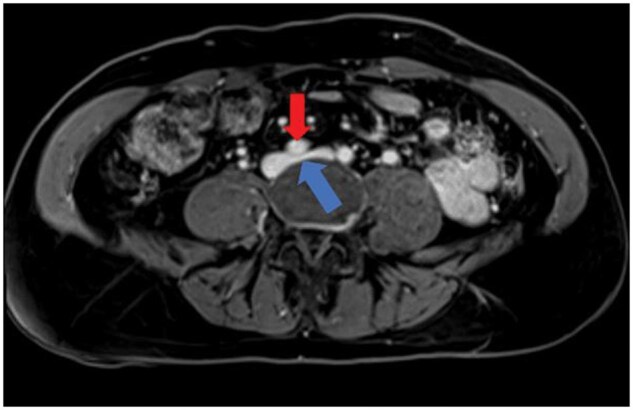

May-Thurner生理(MTP)可导致各种充血综合征,由于右髂总动脉(RCIA)压迫左髂总静脉(LCIV)。这种压迫可能导致通过腰静脉的静脉回流,导致脊髓硬膜外静脉丛(EVP)充血,这可能导致顽固性头痛。本病例报告详细介绍了一例伴有MTP的严重难治性新发持续性头痛患者的临床过程,该患者接受了腰升静脉(ALV)栓塞术。患者为59岁女性,每日持续性头痛3年,多次偏头痛预防治疗和微创手术均无效。影像学研究显示RCIA对LCIV有明显压迫,ALV血流逆行,EVP充血。患者接受了ALV栓塞治疗,症状明显缓解。在22个月的随访中,头痛严重程度降低了80%,患者不再需要常规的头痛药物。此外,通过性腺静脉栓塞治疗相关盆腔充血综合征解决了长期相关的盆腔疼痛和压力。本病例强调了静脉充血在难治性头痛综合征中的作用,并强调了靶向静脉干预的潜力,如栓塞,在其管理中。研究结果扩展了将静脉压迫综合征与头痛病理生理联系起来的新证据,并支持探索干预策略作为选定患者的可行治疗选择。需要进一步的研究来验证这些发现,并为临床实践建立循证指南。

May-Thurner physiology (MTP) can lead to various congestion syndromes due to compression of the left common iliac vein (LCIV) by the right common iliac artery (RCIA). This compression may result in venous reflux through the lumbar vein, leading to congestion of the spinal epidural venous plexus (EVP), which could contribute to refractory headaches. This case report details the clinical course of a patient with severe refractory new daily persistent headache associated with MTP who underwent ascending lumbar vein (ALV) embolization. The patient is a 59-year-old female with a 3-year history of daily persistent headache which failed multiple migraine prevention therapies and minimally invasive procedures. Imaging studies revealed significant LCIV compression by the RCIA, retrograde ALV flow, and EVP congestion. The patient underwent ALV embolization, resulting in significant symptomatic relief. At the 22-month follow-up, headache severity reduced by 80%, with the patient no longer requiring routine headache medications. Additionally, treatment of associated pelvic congestion syndrome through gonadal vein embolization resolved longstanding associated pelvic pain and pressure. This case highlights the role of venous congestion in refractory headache syndromes and underscores the potential of targeted venous interventions, such as embolization, in their management. The findings expand on emerging evidence linking venous compression syndromes to headache pathophysiology and support exploring interventional strategies as viable treatment options for selected patients. Further research is needed to validate these findings and establish evidence-based guidelines for clinical practice.